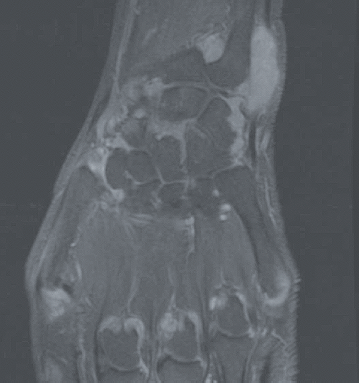

La polyarthrite rhumatoïde (PR) est une maladie auto-immune mais dans laquelle les auto-anticorps que sont le facteur rhumatoïde (FR) et les anticorps anti-peptides citrullinés (ACPA ; également appelés anti-CCP) ne sont pas constants : les PR appelées « séropositives » (FR+ et/ou ACPA+, qu’il conviendrait mieux de dénommer immuno-positives) représentent 75 à 80% des PR. Il reste donc 20 à 25% des PR séronégatives (FR- et ACPA-) dont la reconnaissance précoce est rendue plus difficile par l’utilisation des critères de classification européens-américains ACR/EULAR 2010 où le poids des auto-anticorps est très important (Tableau 1). La question de savoir s’il existe une seule PR avec deux visages ou deux maladies de physiopathologie différente reste débattue. Dans le diagnostic (et le suivi) de ces formes séronégatives, comme dans les formes séropositives, l’intérêt de l’échographie articulaire a été récemment souligné. L’IRM a également un intérêt pour la mise en évidence des synovites mais est ciblée sur une articulation ou un groupe articulaire alors que l’échographie permet une analyse de très nombreuses articulations (Figure 1). Un autre axe d’intérêt est représenté par les formes très précoces de PR, avec cliniquement de simples arthralgies mais associées à des auto-anticorps (FR/ACPA), situation où des essais d’intervention thérapeutique ont été menés récemment où sont en cours.

Figure 1. Exemple d’IRM du poignet et des métacarpo-phalangienne au cours de la PR en poussée